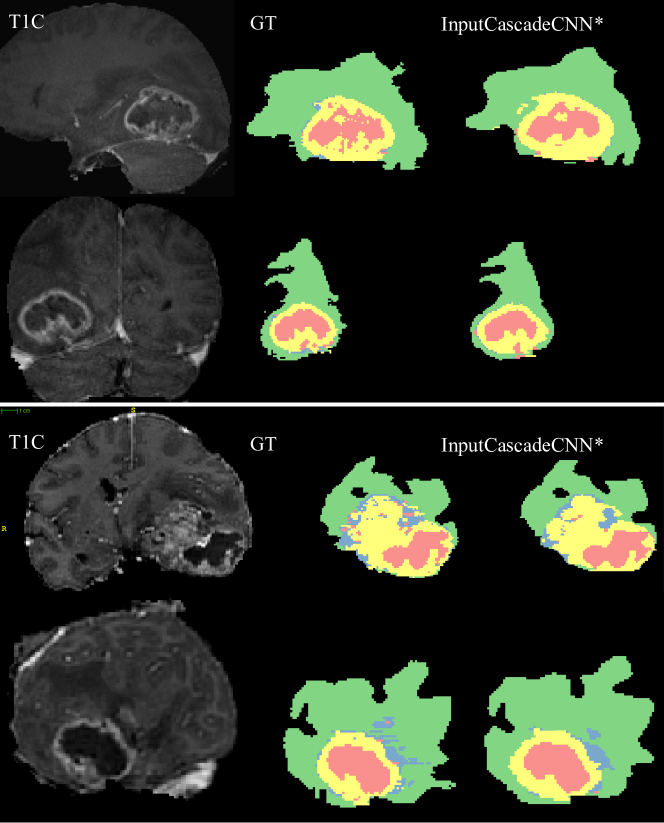

Figure 8: Visual results from our top performing model, InputCascadeCNN* on Coronal and Sagittal views. The subjects are the same as in Figure 7. In every sub-figure, the top row represents the Sagital view and the bottom row represents the Coronal view. The color codes are as follows: \blacksquare edema, \blacksquare enhanced tumor, \blacksquare necrosis, \blacksquare non-enhanced tumor.

Figure 8 shows segmentation results from the same brains (as in Figure 7) in Sagittal and Coronal views. The InputCascadeCNN* model was used to produce these results. As seen from this figure, although the segmentation is performed on Axial view but the output is consistent in Coronal and Sagittal views. Although subjects in Figure 5 and Figure 6 are from our validation set for which the model is not trained on and the segmentation results from these subjects can give a good estimate of the models performance on a test set, however, for further clarity we visualise the models performance on two subjects from BRATS-2013 testst. These results are shown in Figure 9 in Saggital (top) and Axial (bottom) views.